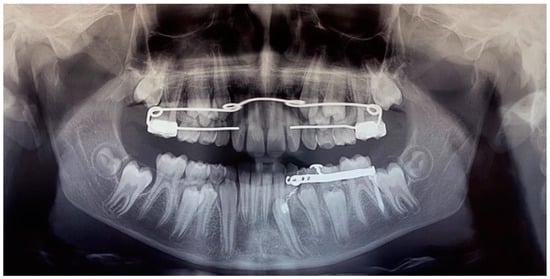

Figure 12. Panoramic radiography of treatment progress (1 year after the first panoramic radiograph).